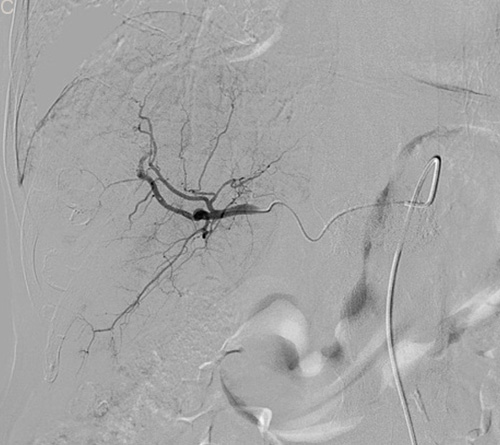

Figure 2: Eighty six-year-old male with a huge hypervascular metastatic pancreatic neuroendocrine tumor treated with multiple cycles of chemotherapy. A. Gd-enhanced T1WI revealed a round enhanced tumor of the right lobe in the arterial phase. B. Tumor staining during arterial phase of DSA: The tumor was nourished by the branches of the right hepatic artery. C. Tumor staining disappeared after TACE therapy. D. Gd-enhanced T1WI 2 image months after drug-eluting microspheres loaded with oxaliplatin chemoembolization showed signal reduction indicating resorption without enhancing residual or recurrent tumor mass.